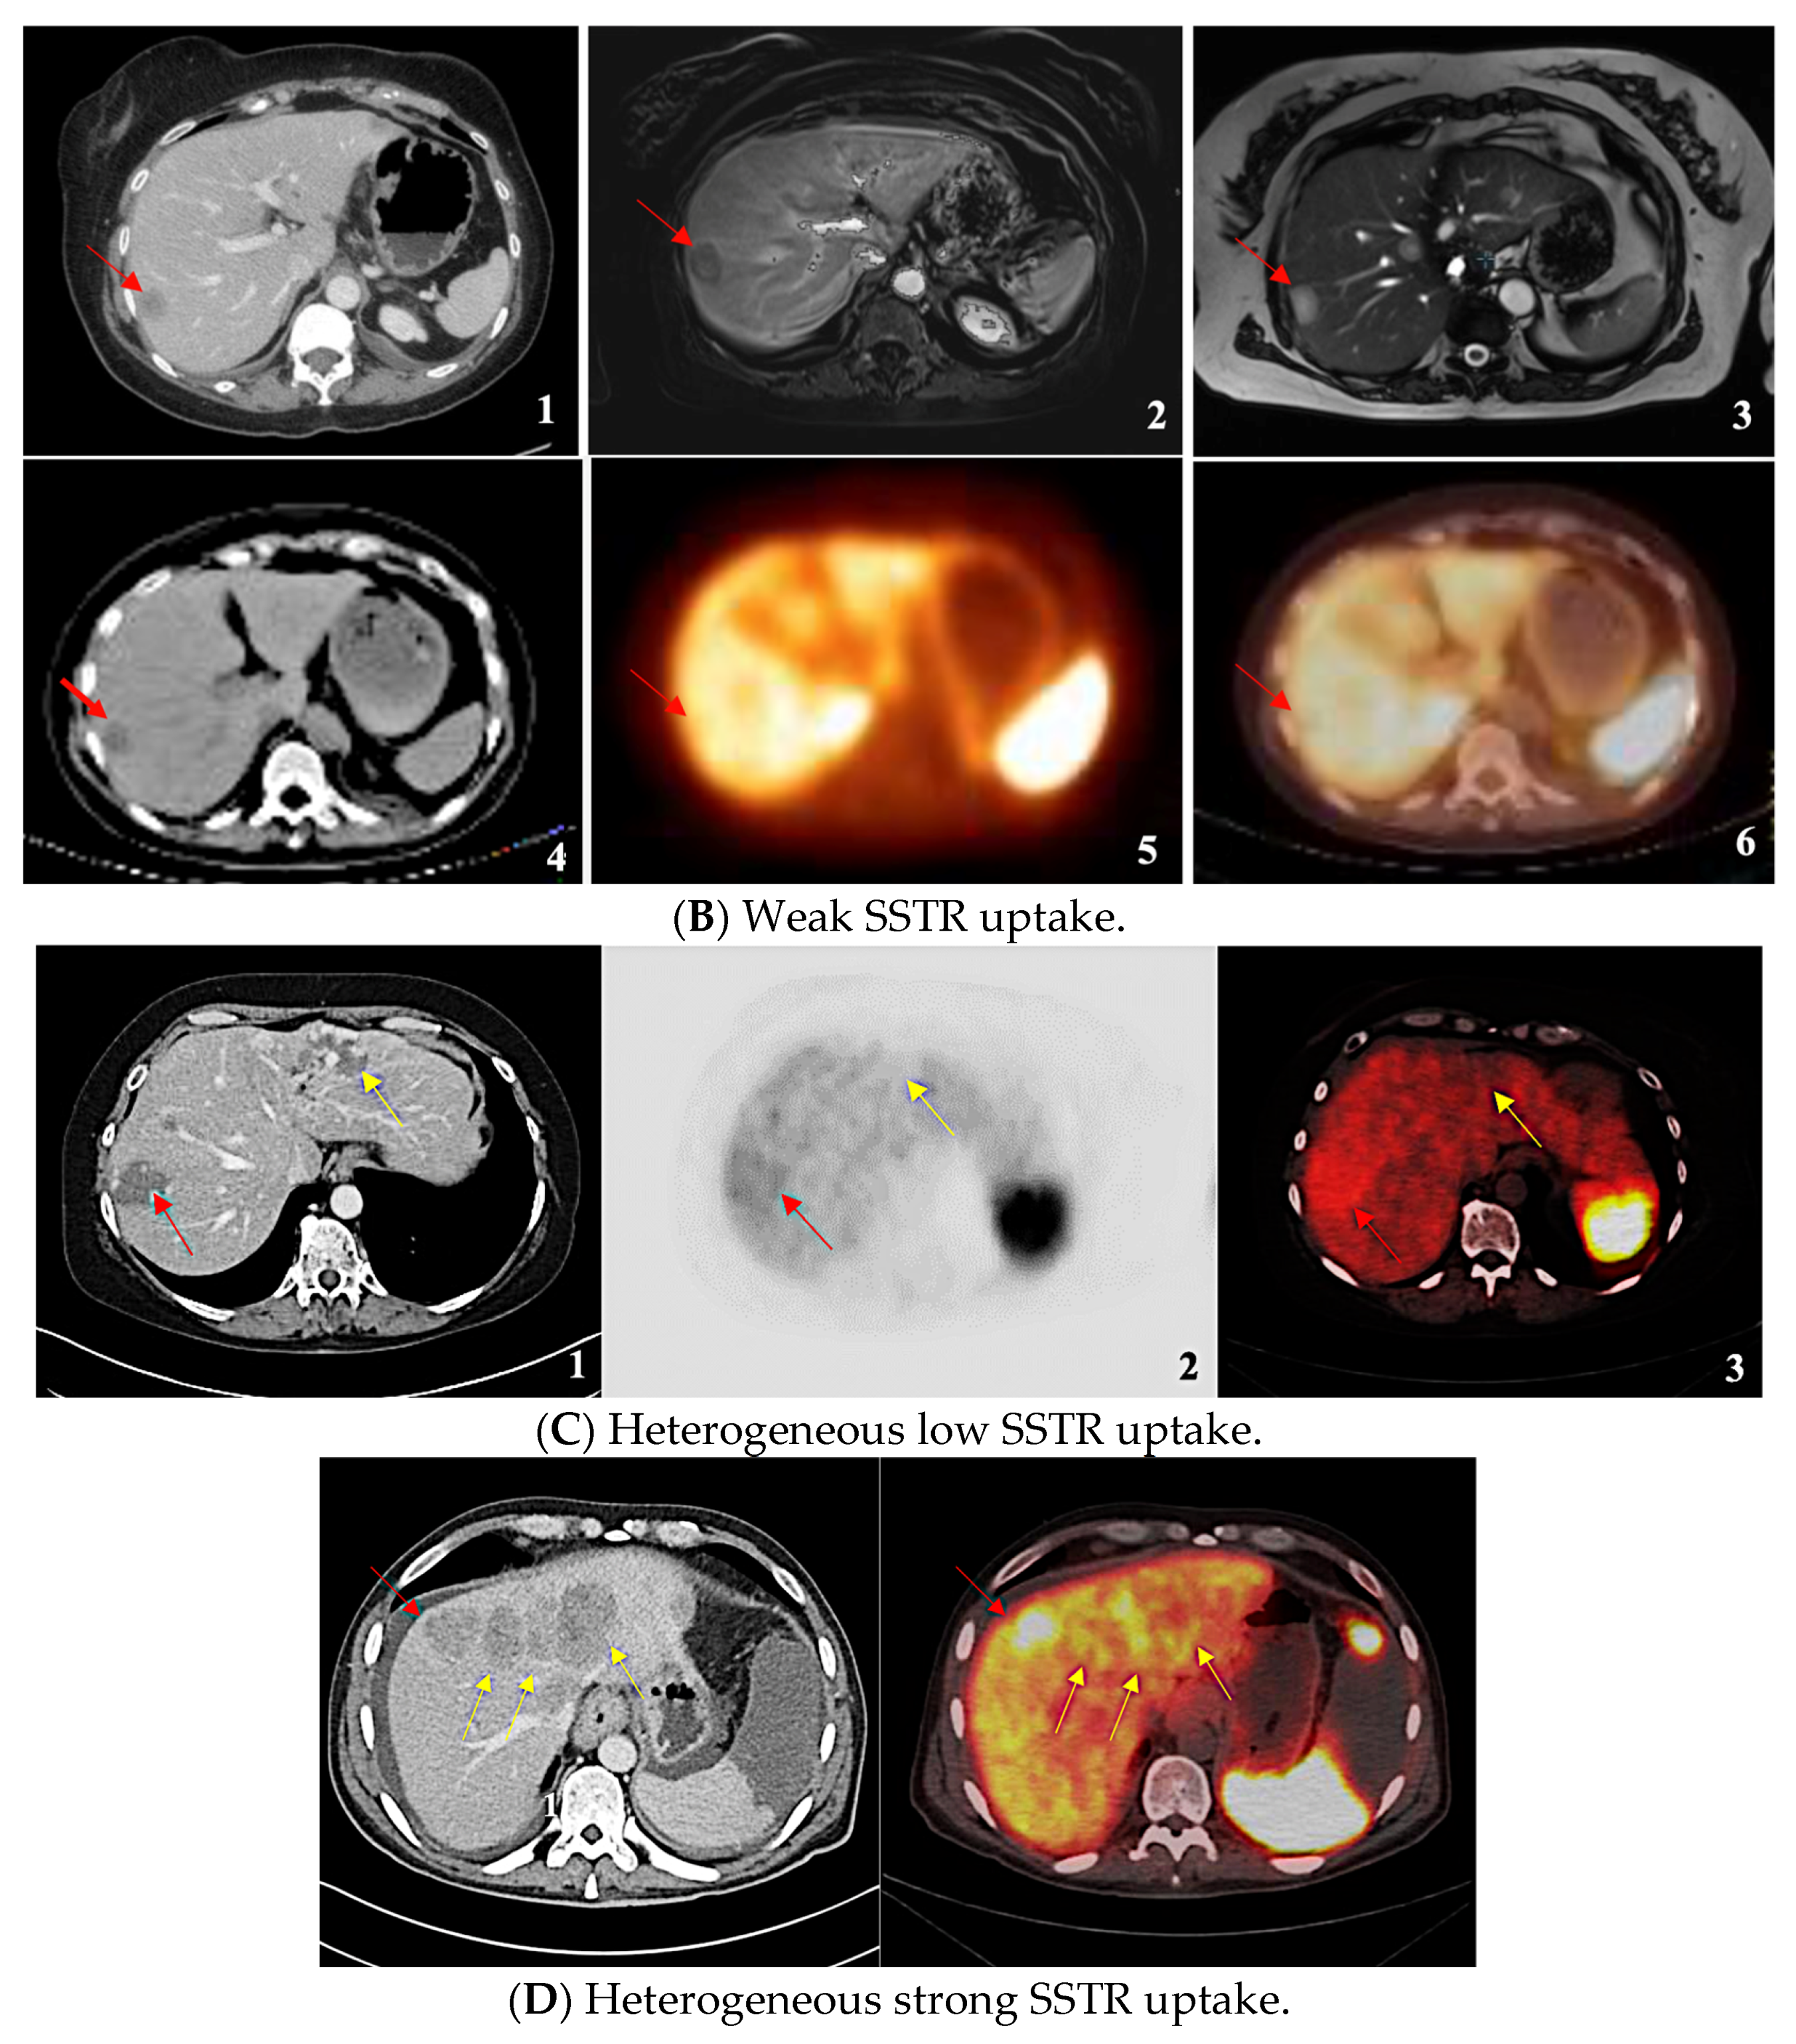

| SSTR Expression Assessment per Study | Krenning Score | Definition |

|---|---|---|

| Negative/Absent | 0 | No uptake |

| Homogeneous Weak | 1 | Much lower than liver |

| 2 | Slightly less than or equal to liver | |

| Homogeneous Strong | 3 | Greater than liver |

| 4 | Greater than spleen | |

| Heterogeneous Low | - | Mixture of absent and less than or equal to liver uptake lesions |

| Heterogeneous Strong | - | Mixture of strongly avid lesions combined with the absence or near absence of SSTR expression in at least one measurable tumor (primary or metastasis). |

| SSTR Expression Assessment per Study | Krenning Score | Definition | Mean SUVmax |

|---|---|---|---|

| Negative/Absent | 0 | No uptake | - |

| Homogeneous Weak | 1 | Much lower than liver | 9 |

| 2 | Slightly less than or equal to liver | ||

| Homogeneous Strong | 3 | Greater than liver | 31.2 |

| 4 | Greater than spleen | ||

| Heterogeneous Low | - | Mixture of absent and less than or equal to liver uptake lesions | 9.5 |

| Heterogeneous Strong | - | Mixture of strongly avid lesions combined with the absence or near absence of SSTR expression in at least one measurable tumor (primary or metastasis). | 42.4 |